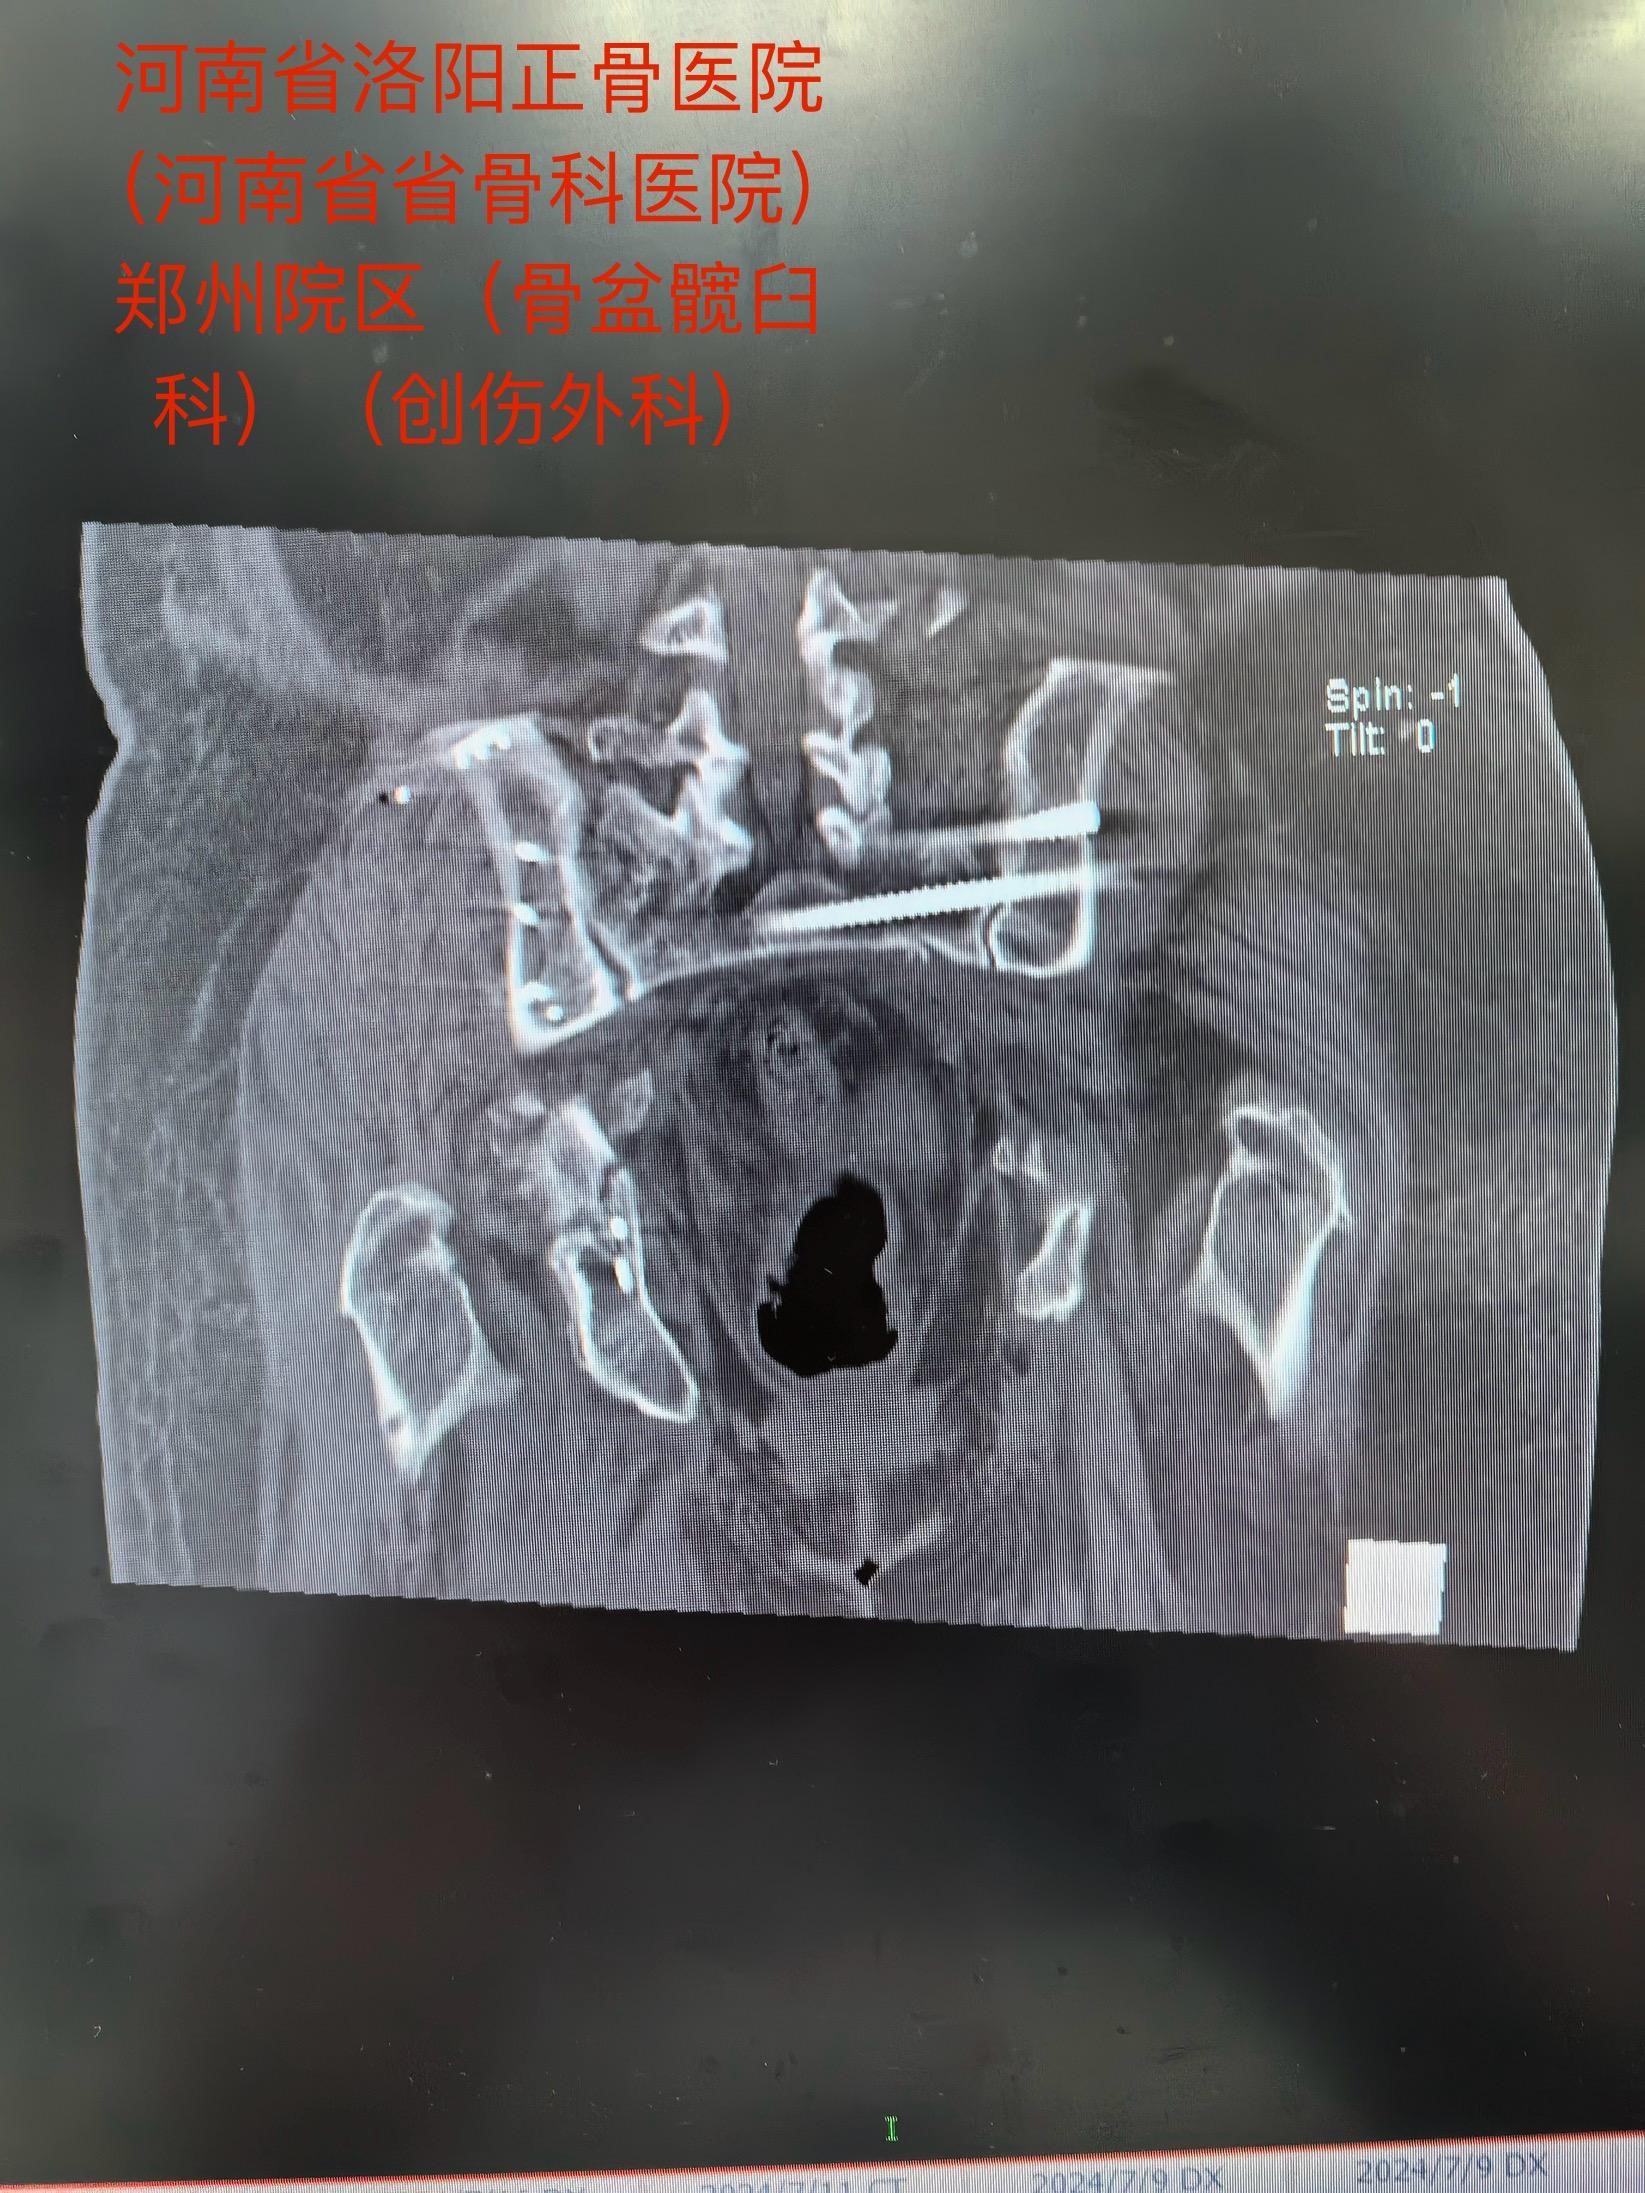

马献忠主任积极倡导加速康复外科理念,对于老年骨盆髋臼骨折患者,他主张积极治疗。面对老人的复杂病情,马献忠主任积极组织多学科会诊,充分讨论,详细制定术前规划,为老人量身定制治疗方案。马献忠主任分两期进行手术:1期,右侧骨盆髋臼行单一髂腹股沟入路进行骨折复位及前后柱的固定。2期,进行左侧的微创骶髂螺钉固定骨盆后环。

在团队的共同努力下,手术顺利开展,术后老人恢复良好,现已顺利出院。